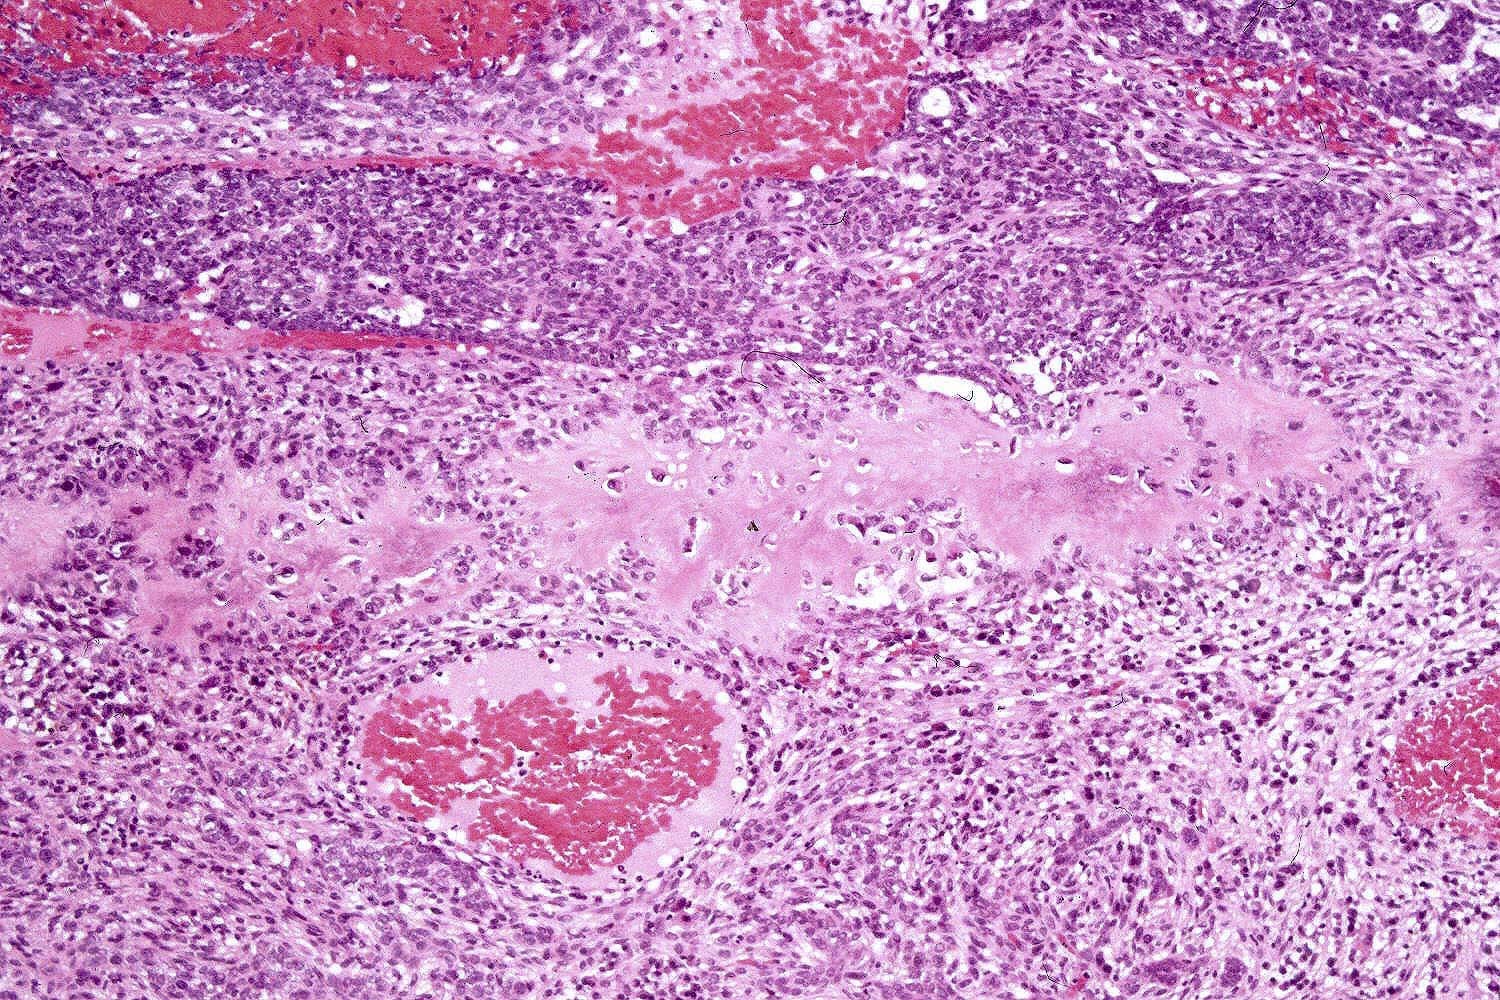

Common variants (Calonje: McKee's Pathology of the Skin, 5th Edition, 2019)

- Nodular and nodulocystic BCC

- Relatively circumscribed mass

- Epidermal or follicular attachment variably present

- Large basaloid lobules with peripheral nuclear palisade

- Lobules may be solid or show central cyst formation due to excessive mucin production

- Fibromyxoid stroma

- Cleft formation between tumor lobules and stroma

- Pleomorphism is generally mild

- Variable mitotic activity and apoptosis

- Sometimes necrosis en masse

Microscopic (histologic) images

Contributed by Antonina Kalmykova, M.D., Phillip H. McKee, M.D., Sate Hamza, M.D., Eduardo Calonje, M.D.,

Wayne Grayson, M.B.Ch.B., Ph.D., James Sampson, M.B.B.S., M.Sc. and Assia Bassarova, M.D., Ph.D.